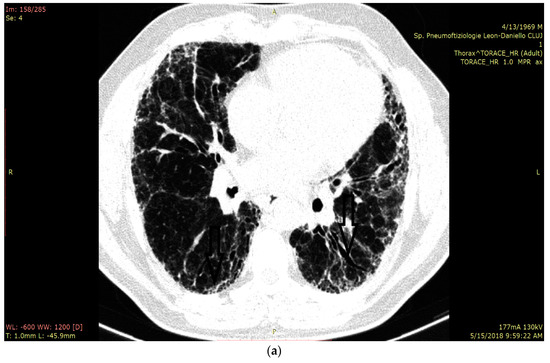

In Figure 3a we present the HRCT changes in the UIP pattern, and in Figure 3b we highlight the presence of B-lines in LUS (Figure 3a,b).

Figure 3.

(a) HRCT imaging in the lung window at the level of middle and lower lobes with subpleural honey combing and fine reticulation, as well as traction bronchiectasis, that confirm UIP pattern (black lines). (b) LUS imaging with multiple B-lines (thin arrow), confirm the fibrotic interstitial syndrome; thick arrow represents pleural line which is not thickened.